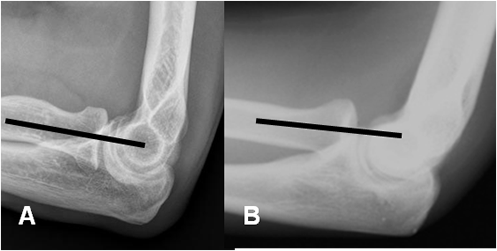

Fig 29. Signo de la línea humeral anterior en Rx lateral.

A: Línea normal, que cruza el capitel.

B: Fractura supracondilea con desplazamiento del capitel, que no es cruzado por la línea humeral anterior.